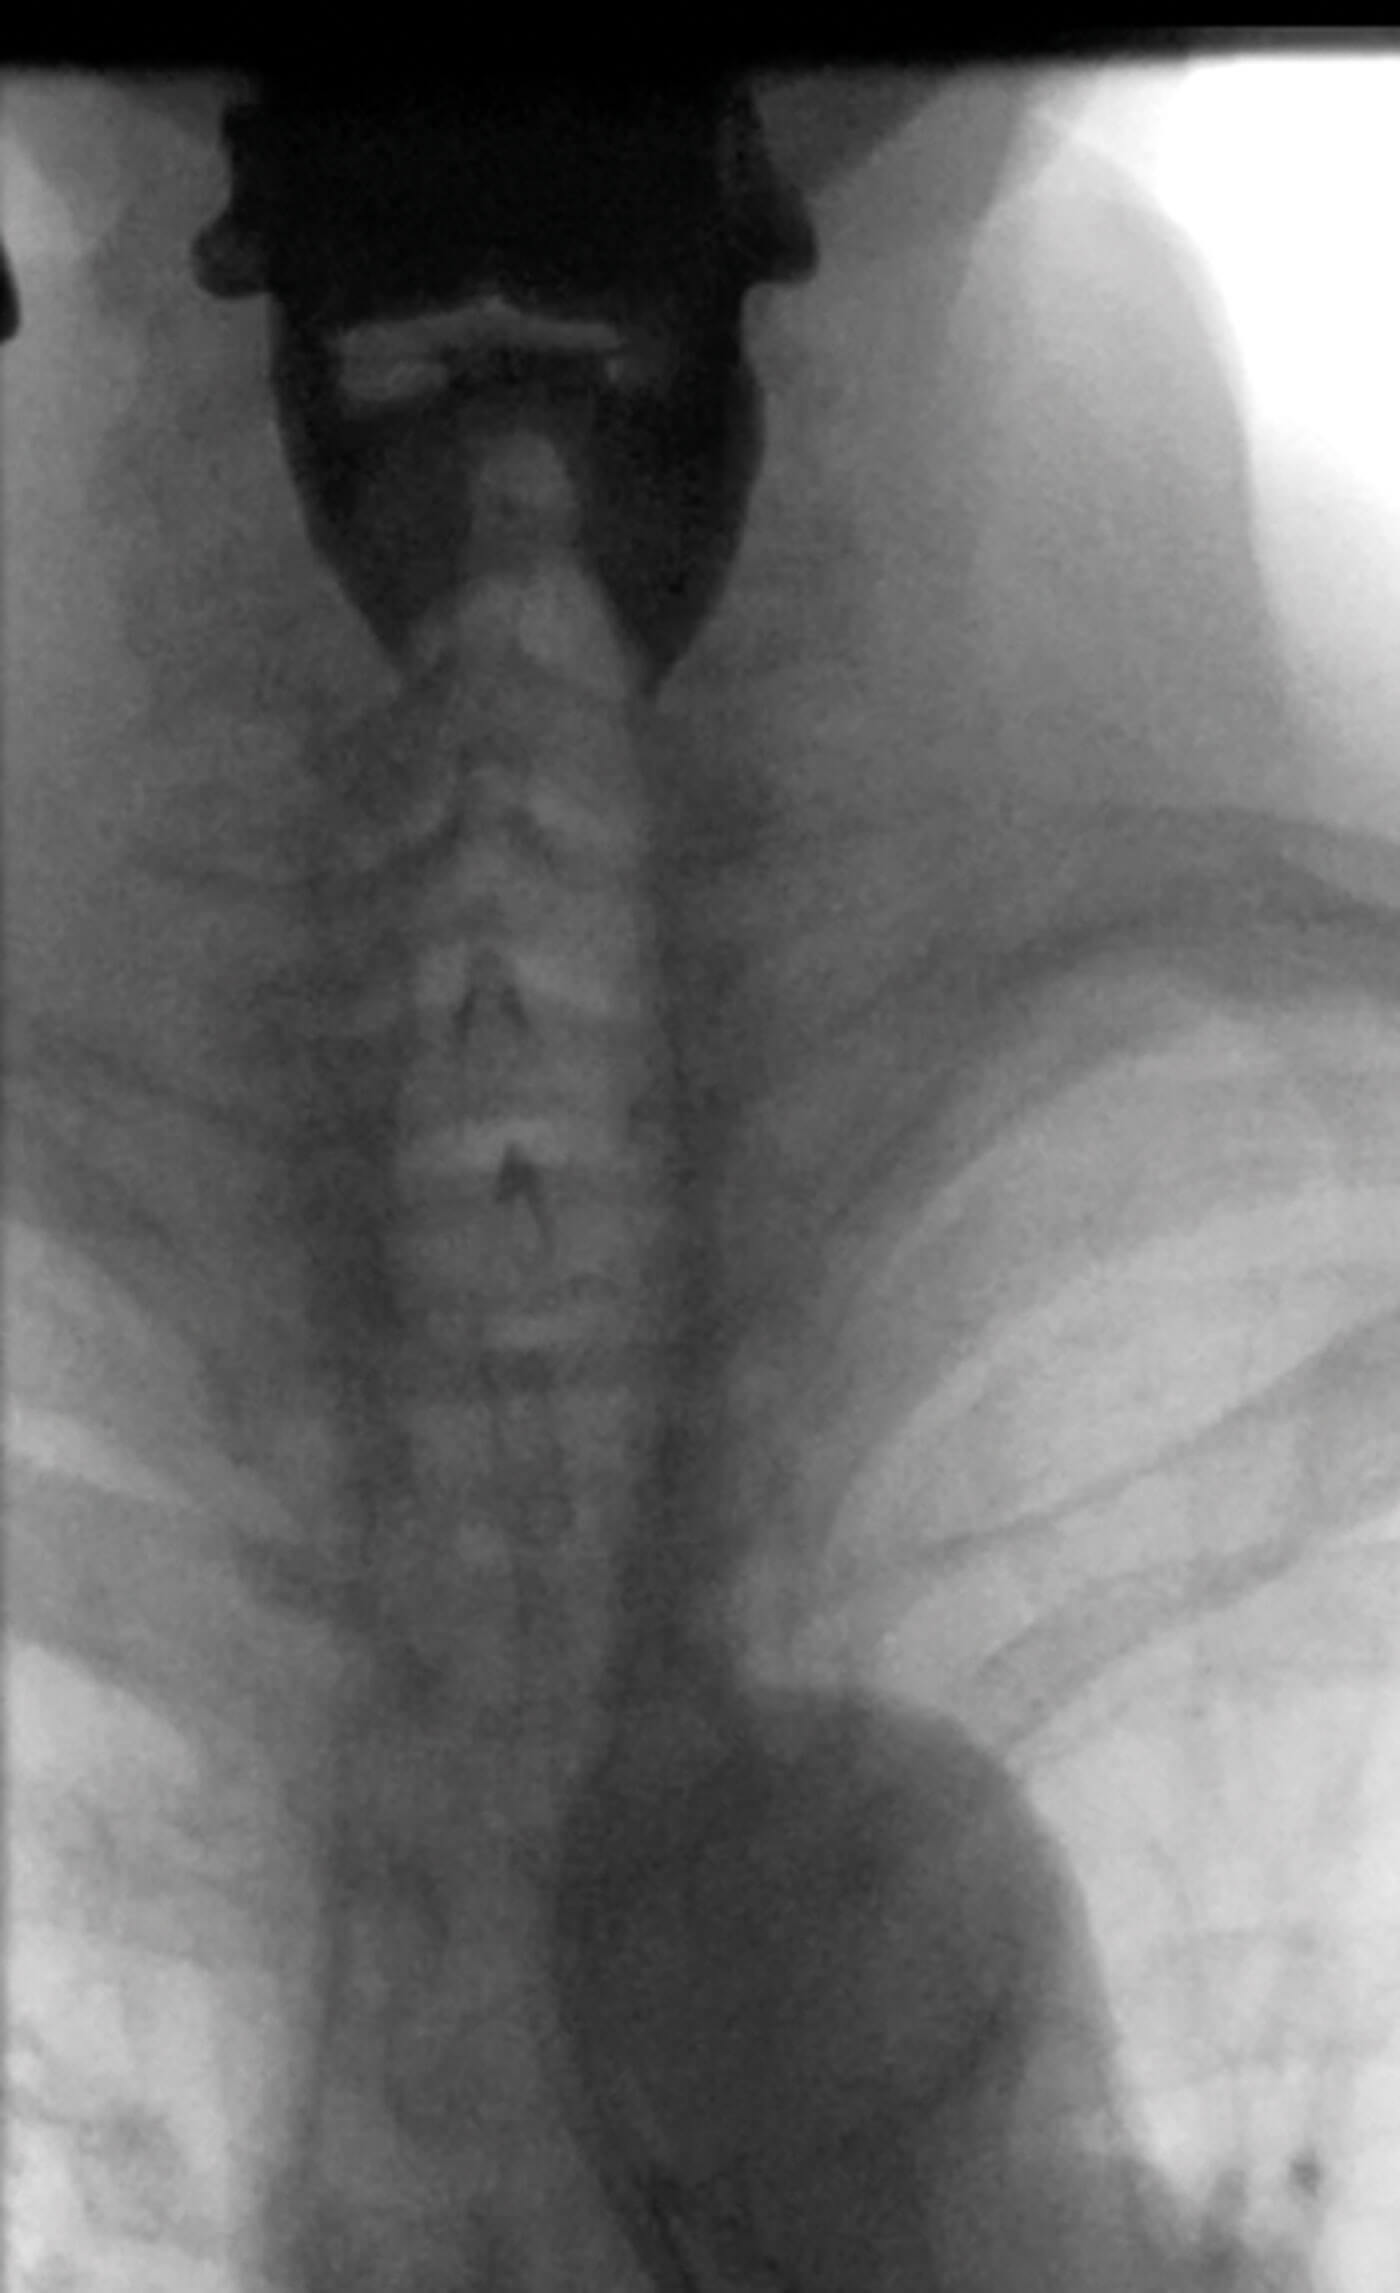

Fluoroscopic lateral view of pharyngoesophageal segmaent

demonstrating upper oesophageal sphincter web.